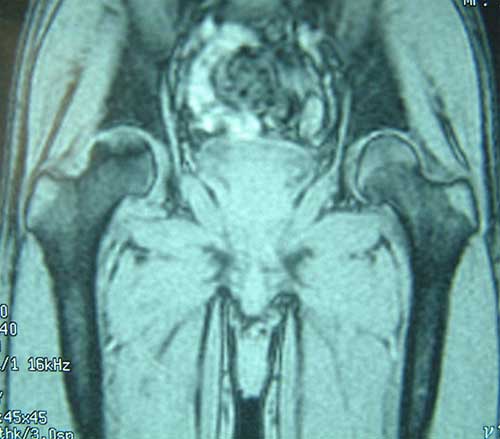

股骨头缺血性坏死MRI显示坏死区          微创手术方法,采用隧道减压刮除死骨

BMP植入,异体骨支撑,恢复形态     手术后24个月X线片,关节塌陷未加重,关节功能良好,无疼痛